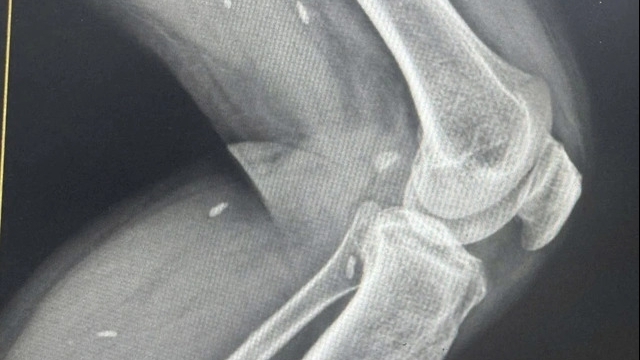

Chụp X-quang cho thấy xương đốt 1 của ngón tay bệnh nhân đã bị bào mòn nặng, kích thước chỉ bằng ngón út và mất khoảng 1/2 thể tích so với ngón tay bình thường.

Ths.Bs Nguyễn Ngọc Linh – chuyên khoa Phẫu thuật tạo hình lý giải: trong dị dạng AVM, dòng máu chảy thẳng từ động mạch sang tĩnh mạch mà không đi qua hệ mao mạch trung gian, khiến máu không tham gia nuôi dưỡng mô mà “chảy tắt” về tim. Dòng chảy sai hướng, mạnh và liên tục này đập trực tiếp lên mô xương nhiều năm liền, gây hiện tượng mòn xương cơ học dù không viêm, không đau.